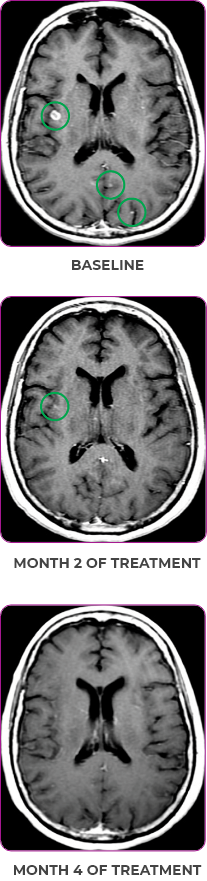

Response to VITRAKVI1

- After 8 weeks on VITRAKVI, all target lesions had disappeared, demonstrating a complete response

- The complete response was sustained over 11 months of treatment with VITRAKVI

- Patient experienced Grade 1 fatigue and mild hepatic enzyme elevation

Response in primary and metastatic lesions1

MRIa imagery of the lungs. Arrow indicates large target lesion in left lung.1

SCAN 1: LUNG

MRIa imagery of the brain. Arrow indicates large target lesion in left lung.1

aMRI, magnetic resonance imaging.

Images courtesy of Dr Fabian Pitoia.